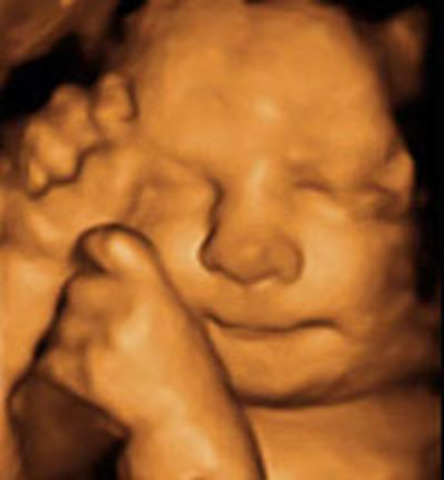

• DESARROLLO FETAL: SEMANA 13 A 16

DESARROLLO FETAL: SEMANA 13 A 16

ULTRASONIDO 16 SEMANAS

Las cuerdas vocales comienzan a formarse. El sentido del tacto se desarrolla. Es capaza de separar los dedos de los pies, flexionar las muñecas, cerrar los puños, girar la cabeza y abrir su boca. En este periodo aumenta su número de reflejos y es capaza de succionar y deglutir. Las piernas ya son más largas que los brazos y mueve sus extremidades con frecuencia.